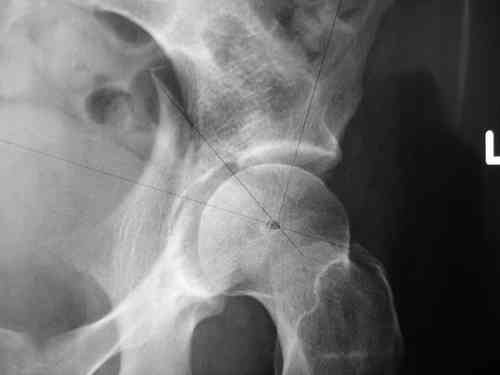

Спасибо за клинические примеры и комментарии. Если честно то просто восхищен представлеными R-ммами (классно сделали!!!). По поводу обсуждаемого больного: конечно КТ и дополнительные R-ммы сделаем. Но хочу напомнить, что после травмы прошло более 6 лет, на сегодняшний день клинически еще и R-ки признаки нестабильности эндопротеза( как бедренного компонента так и чашки). Хочется определиться как делать в аппарате или одномоментно открыто. Лично я склоняюсь к аппаратному лечению на первом этапе.

прилагаю пример с такой же давностью травмы, репонировали аппаратом

задача непростая, если мало опыта в этом деле, подумайте еще раз